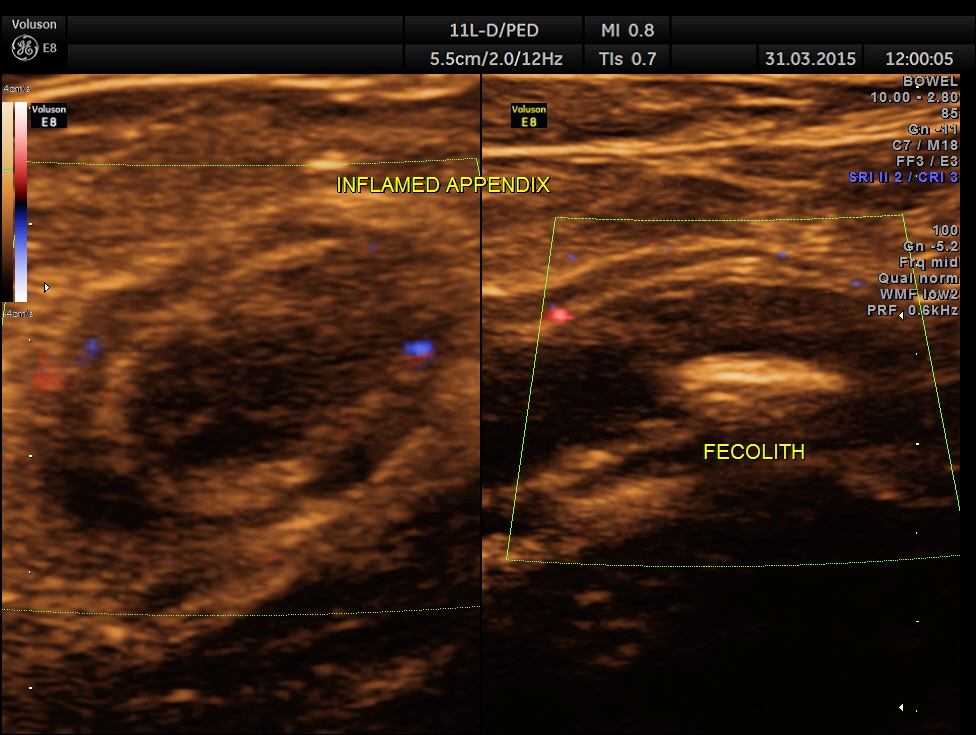

Now this looks more like an inflamed appendix with a prominent fecolith of size 11.4 mms , throwing a shadow.

The following pictures are with a high resolution probe.

The following picture shows the long and short axis views.

This patient had some misleading signs and symptoms . It is always better to establish the ” connection” between the dilated ureter and the kidney. Usually appendix is picked up better with high resolution transducers. But in this patient , it was well picked up with a routine abdominal transducer. The colour doppler was useful in this patient also.